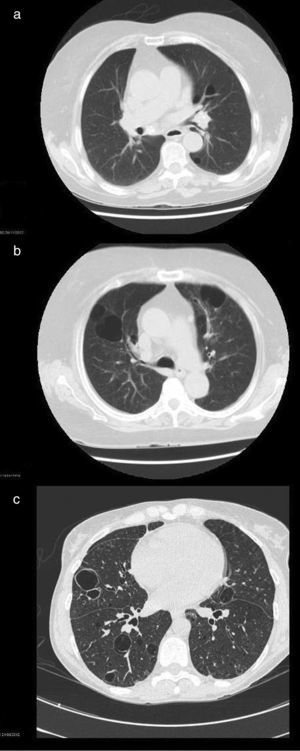

High-resolution computed tomographic study: (a) image showing centrilobular emphysema and cysts; (b) bilateral cystic lung lesions, some with septa in their interior, traction bronchiectasis in both lower lobes, areas of centrilobular and paraseptal emphysema and zones of fibrotic tissue; and (c) image showing multiple bilateral thin-walled pulmonary cysts.

Patient no. 1The first patient was a 74-year-old woman with an 18-year history of pSS. She presented with extraglandular manifestations, such as the vasculitis, polyarteritis nodosa. The most notable laboratory findings were hypergammaglobulinemia and anti-Ro and anti-La antibodies. She was being treated with oral azathioprine at a dose of 50mg/day. During follow-up she developed functional dyspnea grade II. The results of respiratory function tests were normal, and HRCT of the thorax revealed centrilobular pulmonary emphysema, predominantly in upper lobes, and images of thin-walled cysts predominantly in lower lobes (Fig. 1a). The same treatment was maintained, and there were no changes in the pulmonary lesions in subsequent visits.

This patient was a 46-year-old woman with a 20-year history of pSS and diagnosed with IgA kappa myeloma. Her extraglandular manifestations were anemia and leukocytoclastic vasculitis, as well as polyarteritis and parotid gland enlargement. She was being treated with hydroxychloroquine (HCQ) 200mg/day, oral pilocarpine 15mg/day and rituximab every 6 months. Laboratory tests revealed elevated acute-phase reactant levels, anemia and lymphopenia, as well as hypergammaglobulinemia with an elevated IgG level and a monoclonal IgA kappa component. Tests for rheumatoid factor (RF), as well as anti-Ro and anti-La antibodies, were positive. During follow-up, she developed dyspnea on heavy exertion. Respiratory function tests revealed a mild restrictive ventilatory defect with a slightly reduced diffusing capacity of the lung for carbon monoxide (DLCO), and HRCT of the thorax showed bilateral cystic lung lesions—some with septa in their interior—predominantly in the bases, traction bronchiectasis in both lower lobes, areas of centrilobular and paraseptal emphysema in upper lobes, together with linear opacities and areas of fibrotic tissue in both lung bases (Fig. 1b). No modifications were made in her treatment, and there were no changes in the cystic lesions in subsequent visits.

Patient no. 3The third patient was a 78-year-old woman with a 15-year history of pSS who was also diagnosed with cutaneous amyloidosis. The manifestations were predominantly glandular (xerostomia and xerophthalmia), and there was no extraglandular involvement. She was receiving oral HCQ 200mg/day. The laboratory tests revealed elevated acute-phase reactant levels, polyclonal hypergammaglobulinemia with an elevated IgG level, and positive tests for RF and anti-Ro and anti-La antibodies. During follow-up, she reported dyspnea on moderate exertion and, thus, underwent respiratory function tests, which revealed a mild restrictive ventilatory defect, with a severe reduction in DLCO. Thoracic HRCT (Fig. 1c) showed multiple bilateral thin-walled pulmonary cysts, with no evidence of nodules or changes in the air space. The findings were the same in subsequent visits.